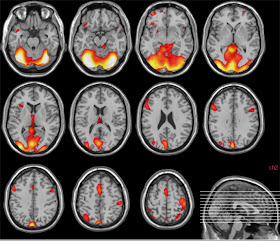

(Actividad cerebral en respuesta a emociones faciales.

Imágenes de resonancia magnética funcional tomada de un artículo científico)